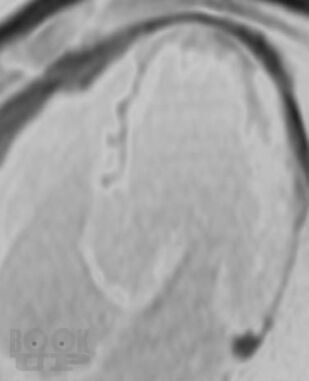

Монография представляет результаты оригинальных исследований нового диагностического метода в кардиологии – контрастированной магнитно-резонансной томографии миокарда у пациентов с ишемической болезнью сердца. Изложены патофизиологические основы методов контрастирования миокарда с помощью парамагнитных контрастных препаратов, основные методики, применяемые в клинике. Представлена визуальная семиотика ишемических повреждений миокарда, в том числе в динамике хирургического лечения – при аорто-коронарном шунтировании и аневризмэктомиях. Представлены результаты использования контрастированной МРТ при желудочковых нарушениях ритма сердца. Констатируется, что сегодня контрастированная МРТ заняла место метода выбора в оценке жизнеспособности сердечной мышцы, заменив радионуклидные исследования. Монография иллюстрирована более чем 100 рисунками и МР-томограммами.